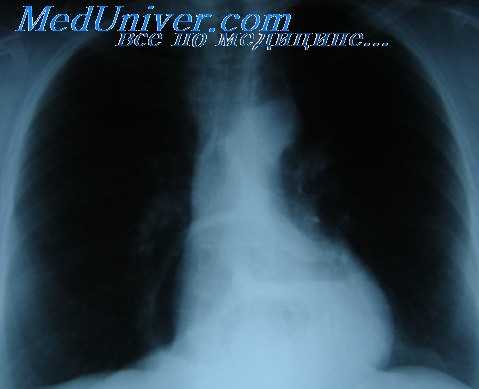

- Лучевая диагностика. Рентгенография и КТ грудной клетки являются наиболее информативными методами исследования диафрагмы. На рентгенограмме визуализируется высокое расположение одного из куполов (уровень II–V ребра). При рентгеноскопии обнаруживается парадоксальное движение диафрагмального свода. Использование контраста позволяет выявить перегибы пищевода, желудка, смещение органов пищеварения кверху. КТ наиболее точно определяет степень релаксации, помогает распознать вторичную патологию внутренних органов.